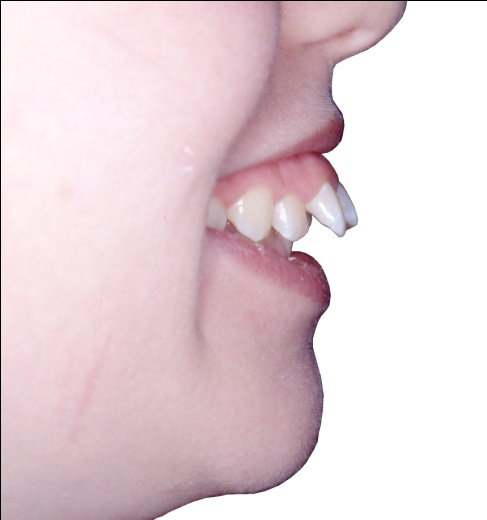

2 - Quand l’orthodontie redessine le visage

Avant traitement, le sourire de profil montre des dents projetées hors de la cavité buccale, avec une incompétence labiale marquée et un profil cutané présentant une biprochélie importante associée à un angle nasolabial très fermé. Après traitement, la transformation est spectaculaire : les dents sont repositionnées dans la bouche, les lèvres se ferment naturellement au repos, le profil est harmonisé, moins protrusif, et l’angle nasolabial a retrouvé une ouverture normale.